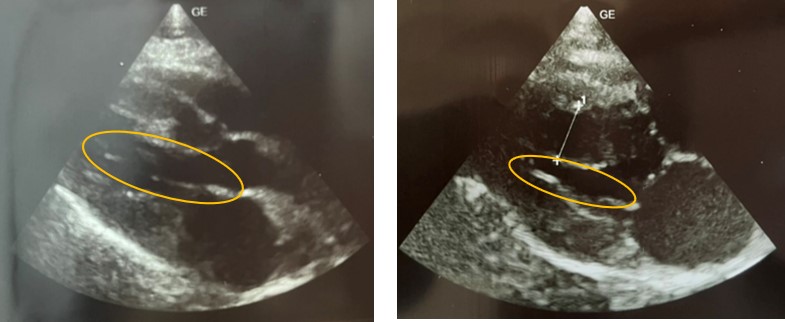

当院でも心臓病を疑うような症状がなかったにもかかわらず、偶然レントゲンを撮影したことで心臓病が見つかり治療中のねこちゃんがいらっしゃいます。

右側が肥大型心筋症のねこちゃんのレントゲン写真です。左側に写真に比べてオレンジの枠で囲った心臓の大きさが大きくなっているのがわかります。